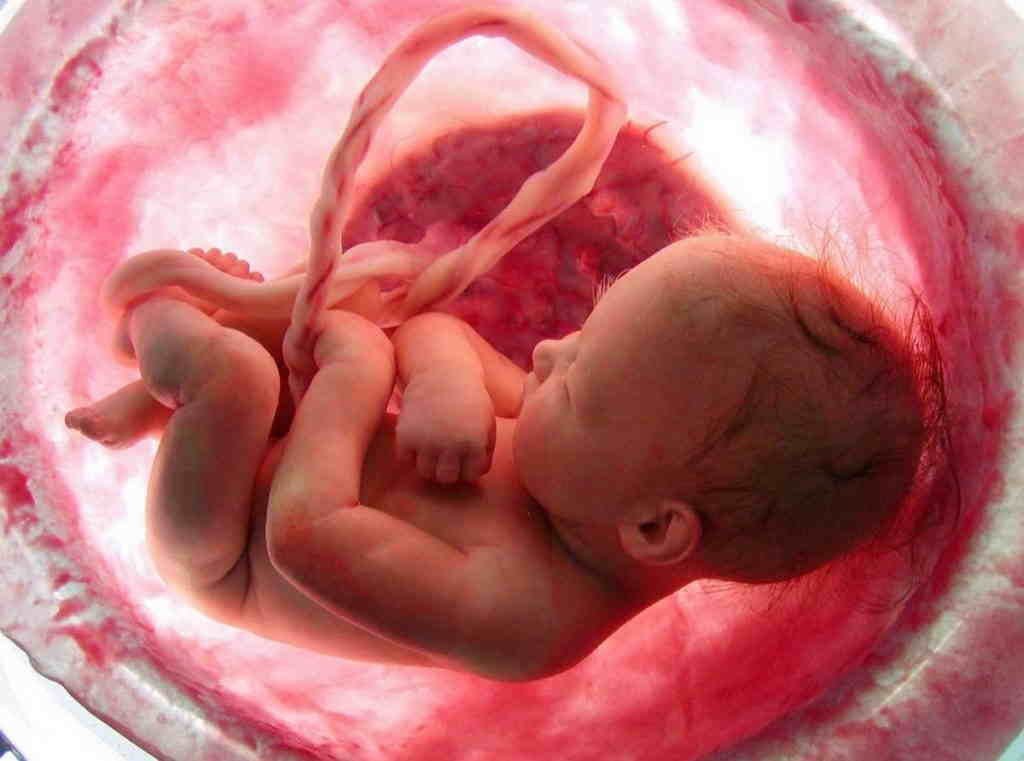

Оптимальный срок для проведения трёхмерного ультразвукового исследования — с 24-й по 28-ю неделю беременности. Плод на этом сроке уже полностью сформирован, и можно детально рассмотреть личико, все части тела и половые органы. А будущие родители получат первую фотографию своего крохи.

При трёхмерном УЗИ изображение получается объёмное, трёхмерное, но статичное. Теперь мы уже можем познакомиться с малышом: увидеть его черты лица, мимику и даже как он зевает или улыбается.

Первая фотография малыша — это изображение, получаемое при 3Д УЗИ